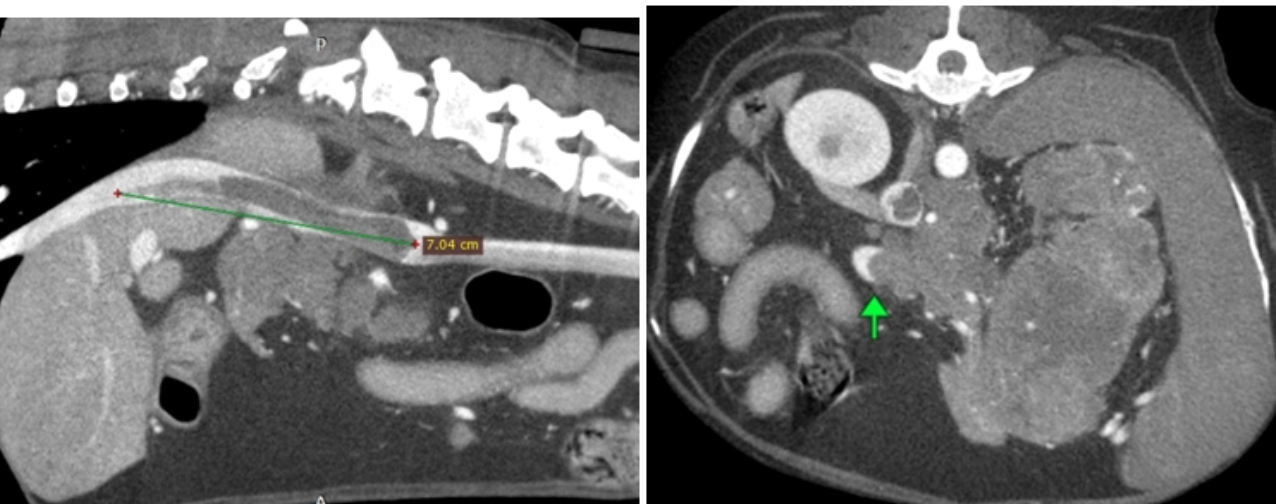

CT (Computed Tomography)

There are many indications for CT scan in animals - such as further evaluation of the nasal cavity, checking for ectopic ureters, finding abnormal vessels, etc.

Cat with a congenital liver shunt

Dog with invasive adrenal mass